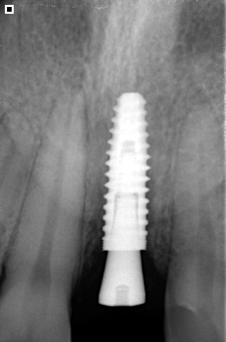

Reemplazamos la pieza dental original por una fabricada en Titanio biocompatible que se introduce en el hueso de la mandíbula, sobre ésta nueva raíz se fija una pieza de metal y cerámica (corona) resistente que se iguala en color y forma con el fin de brindar un aspecto lo más natural posible.

- Implante fabricado en Titanio Grado V de la más alta pureza.

- Reemplaza la raíz del diente y evita la perdida de hueso.

- Indicado para adultos y tercera edad.

- Respaldo casa de implantes SIN